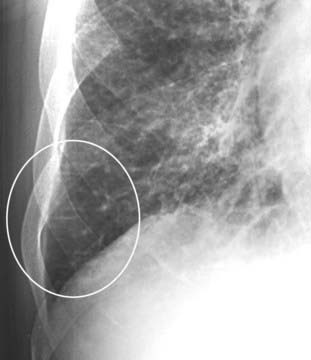

Figure 9-10 Kerley B lines.

Interlobular septae are not visible on a normal chest radiograph but can become visible if they accumulate excessive fluid. First described by neurologist/radiologist Peter James Kerley, they are very short (1-2 cm long), very thin (about 1 mm) horizontal lines perpendicular to and abutting the pleural surface (white oval).